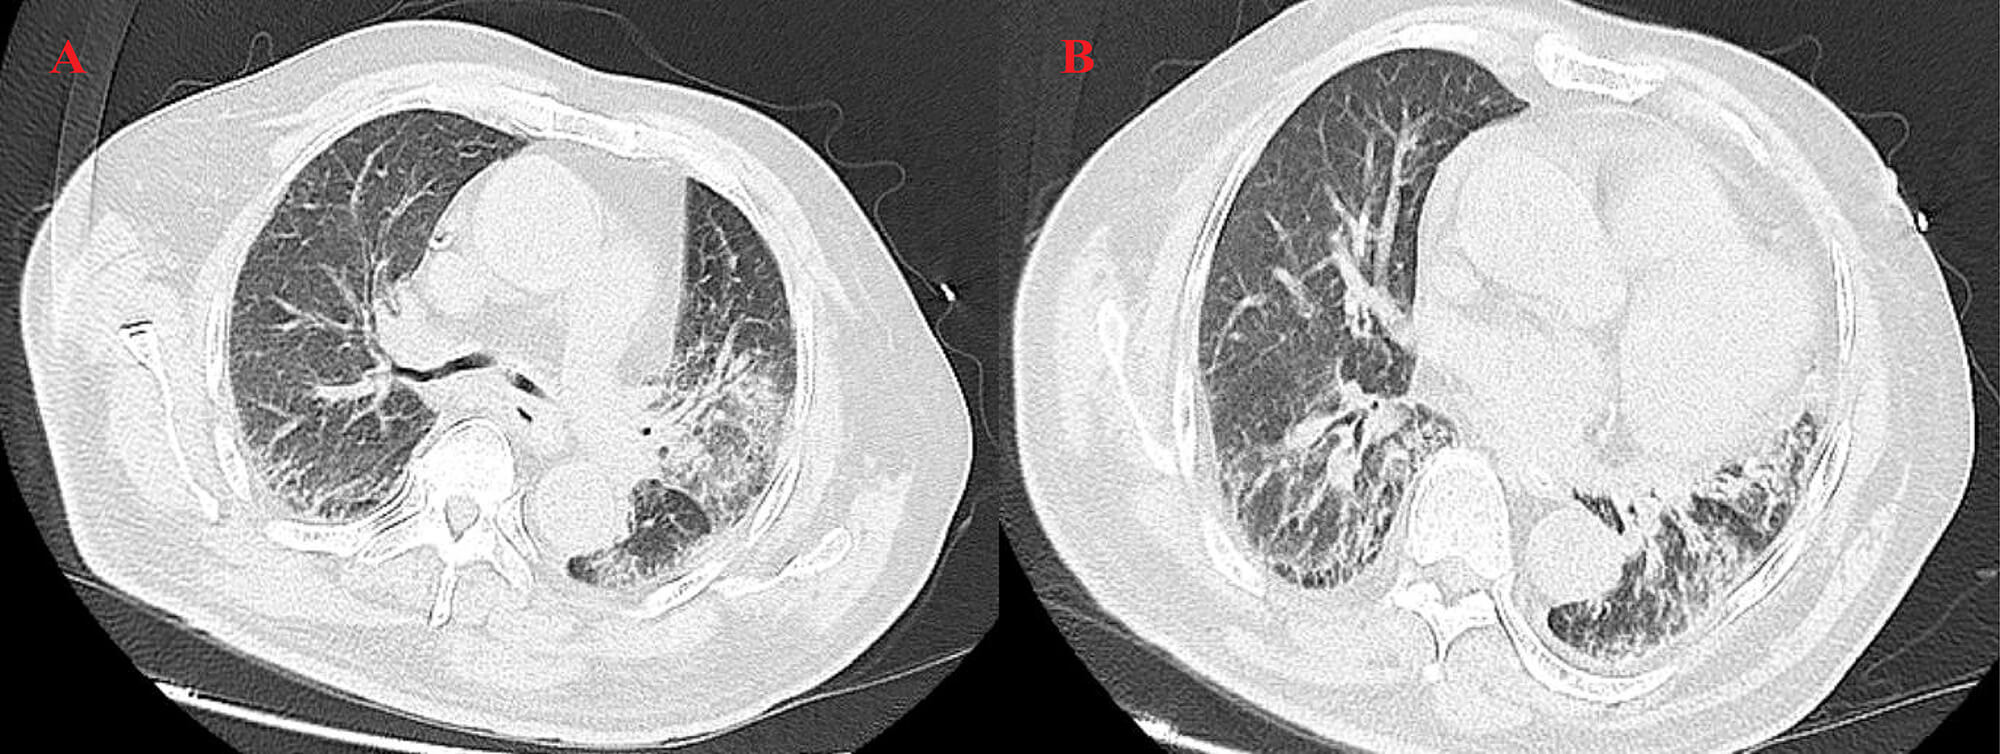

High-resolution computed tomography (HRCT) (Fig. 3) revealed patchy opacities in the left upper and right lower lobes, accompanied by multiple enlarged hilar and mediastinal lymph nodes (Fig. 4), interstitial inflammation in both lungs (Fig. 5), and a small pleural effusion. These findings were consistent with residual tumor and local progression following treatment for extensive-stage SCLC, demonstrating characteristic imaging features of SCLC.

Fig. 3.

HRCT on 23 April 2025. This chest scan showed patchy consolidation in the left upper lobe (A) and right lower lobe (B), with mediastinal lymphadenopathy.